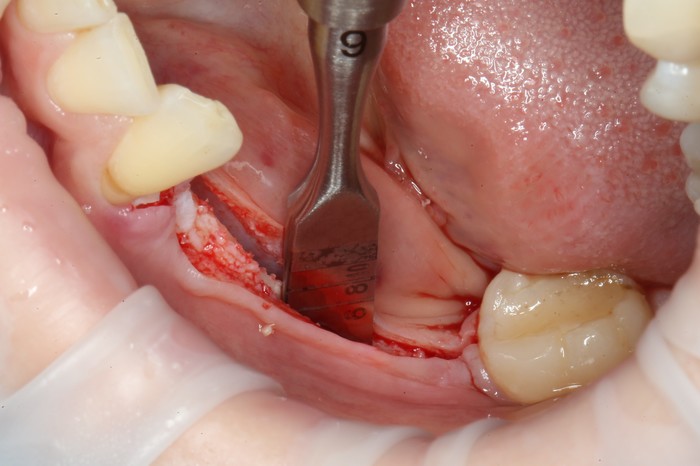

Уже на следующий день была запланирована имплантация.

Дабы не перегружать вас обилием одинаковых картинок, я оставлю один рентгеновский снимок, но отмечу, что установка имплантатов на верхней и нижней челюсти проводилась с разницей в 10 дней.

На верхней челюсти было дополнительно удалено два боковых резца с одномоментной установкой имплантатов, так же они были установлены в области четверок и шестых зубов. Дополнительно было проведено наращивание костной ткани - двусторонний синус - лифтинг. О том, что это такое, можно почитать ТУТ и ТУТ.